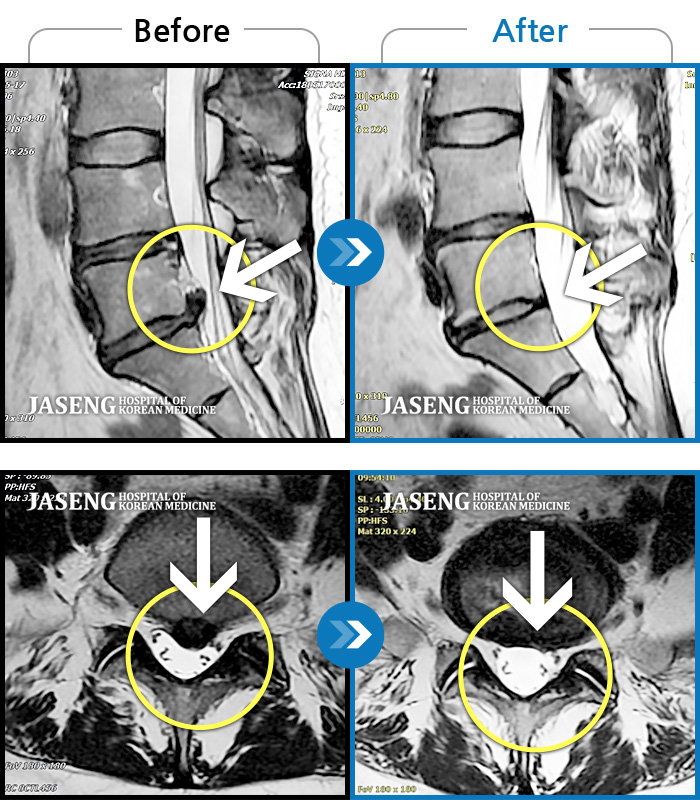

허리디스크

부천 · 최요섭 원장

양측 허리와 골반 통증, 양측 다리 저림

촬영시기

2018.05.17 ~ 2019.10.17

2019.12.13